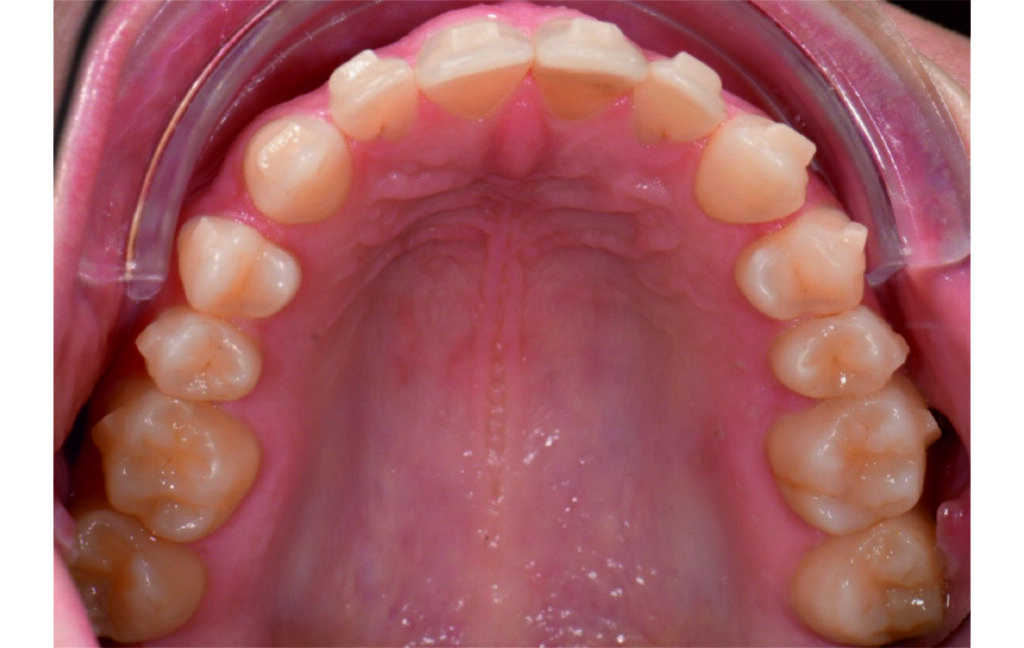

Initial Photos and datas

Angle Class II 2mm on the right, Angle Class II 2mm on the left, light mandibular asymmetry to the right, lower central line 1mm to the right, upper central line 1,5mm to the left, 1mm overjet and overbite. Sagittal asymmetry of upper dental arch. Light crowding upper and lower frontal segments, severe attrition of posterior teeth, night bruxism. Normal sagittal position of both jaws, high angle case, steep mandibular ramus,excessive lower facial height, open bite tendency.

Alignement and expansion 2mm per quadrant.

The case initially presented as a moderate Class II on the right and a Class II tendency on the left, with tapered dental arches and an anterior open bite extending to tooth 26 in segment II.

In segment I, the open bite reached up to the first premolar.

A 1.5 mm deviation of the upper dental midline to the patient’s left was noted, along with a slight mandibular midline shift to the right, likely due to asymmetrical mandibular growth observed in the facial structure. Severe mesial rotations of teeth 16 and 26 were evident in the initial records. As derotation of 16, 26, 17, and 27 progressed up to aligner 16, the premolars in segments I and II moved distally, resulting in a bilateral Class I relationship, as intended in the initial treatment plan.